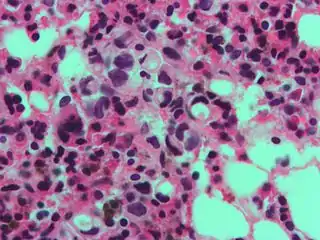

A signet ring-like foamy macrophage, which may mimic a cancer cell, but the texture of the nucleus is similar to that of a normal macrophage. High magnification micrograph showing signet ring cells, with clear cytoplasm, in metastatic breast carcinoma. H&E stain.

High magnification micrograph showing signet ring cells, with clear cytoplasm, in metastatic breast carcinoma. H&E stain._PAS_stain.jpg.webp) Signet ring cells (magenta) stained with PAS in a gastric signet ring cell carcinoma.